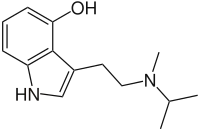

Substituted tryptamines, or serotonin analogues, are organic compounds which may be thought of as being derived from tryptamine itself. The molecular structures of all tryptamines contain an indole ring, joined to an amino (NH2) group via an ethyl (−CH2–CH2−) sidechain. In substituted tryptamines, the indole ring, sidechain, and/or amino group are modified by substituting another group for one of the hydrogen (H) atoms.

| Chemical structure | Short Name | Origin | Ring Substitution | RN1 | RN2 | Full Name | CAS Number |

|---|---|---|---|---|---|---|---|

| MiPT | artificial | H | CH3 | CH(CH3)2 | N-Methyl-N-isopropyltryptamine | 96096-52-5 |

| 4-MeO-MiPT | artificial | 4-OCH3 | CH3 | CH(CH3)2 | 4-methoxy-N-methyl-N-isopropyltryptamine | 96096-53-6 |

| 4-HO-MiPT | artificial | 4-OH | CH(CH3)2 | CH3 | 4-hydroxy-N-isopropyl-N-methyltryptamine | 77872-43-6 |

| 5-MeO-MiPT | artificial | 5-OCH3 | CH3 | CH(CH3)2 | 5-methoxy-N,N-methylisopropyltryptamine | 96096-55-8 |